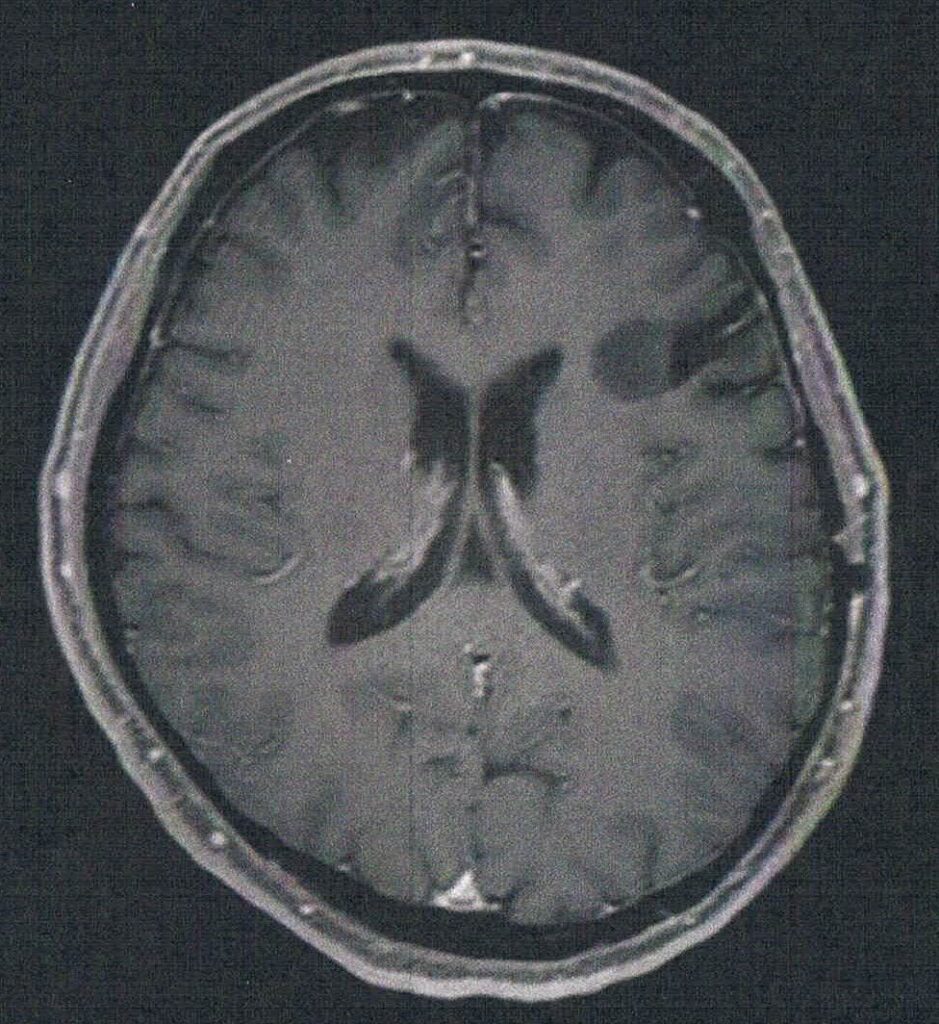

- 造影剤を注射してMRI検査

- 年レベルでおおきくなっている

- 手術して取りに行く